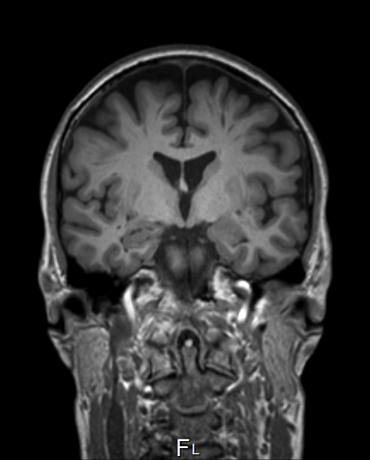

Brain researchers, like geographers, need maps and coordinate systems to navigate the brain and communicate their observations to each other. On a map of the brain, we can superimpose types of neurons, neurotransmitters, enzymes, connectivity, and functional data.

For more than 30 years world-renowned brain cartographer Scientia Professor George Paxinos AO has been relentlessly focused on mapping the brain – not only in humans, but rodents, primates and even birds. These exhaustive definitions are then collected together in atlases illustrating regions and tracts of the whole brain, allowing researchers to generate models of disease and analyse behaviour, and enabling neurosurgeons to ensure accurate and precise incisions.

This work has led to the discovery of 94 hitherto unknown regions since the creation of the first brain atlas more than 30 years ago. Professor Paxinos’ atlases are used internationally as the standard guides for scientific work, as well as by neurosurgeons to target small deep lying structures in the brain.